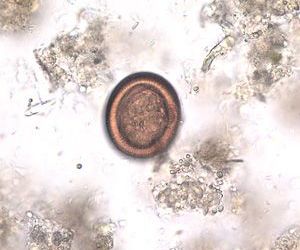

寄生虫~エキノコックスとは

ポイント

• 寄生虫エキノコックスの卵を経口摂取→感染

• 予報方法(1)山菜・野等の食材をよく洗う

• 予報方法(2)川・沢の生水を飲まない